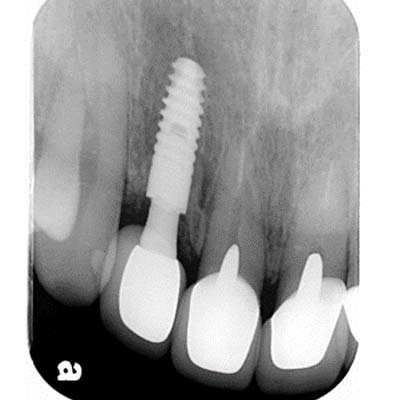

根尖X光片

"4個月骨整合完成後,利用植牙支台齒,製作全瓷冠,恢復外觀"

裝戴正式假牙

8年追蹤